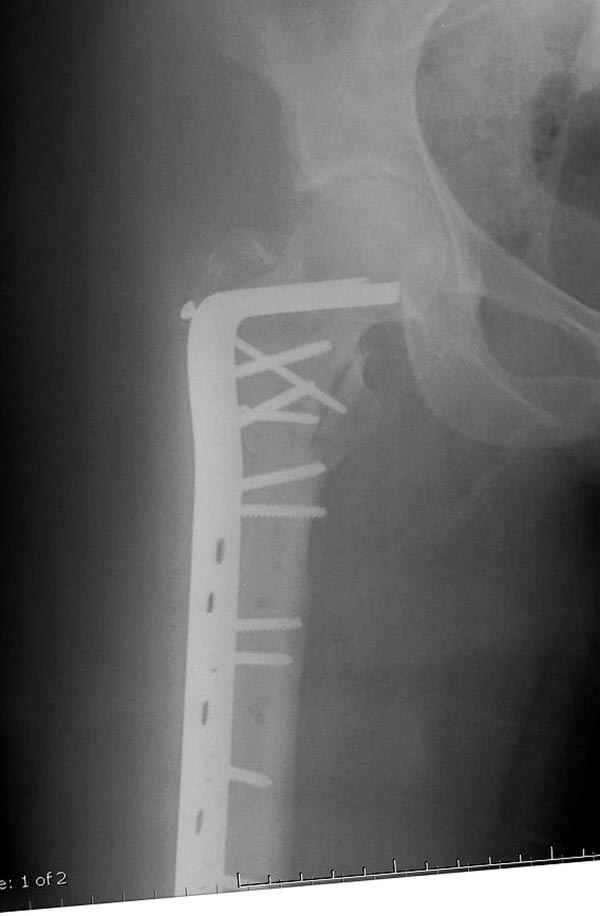

Да, сейчас это и у нас самый напрашивающийся выбор. Сделали гвоздем ChM, картинки в приложении.

У молодых реконструкционный гвоздь самое то. При остеопорозе надо что-то помассивнее.